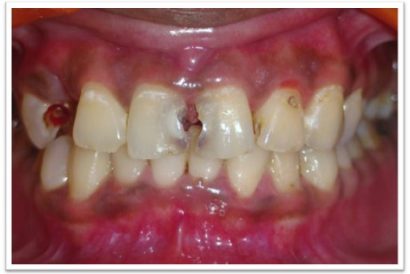

Patient Name:Padma Harkar

Tooth Involved : 11 12 13 21 22 23

Diagnosis : Fluorosis

Treatment : Direct Composite Veneers

Restoration: Direct Composite Using Nanohybrid composite

Stains masked using IVOCLAR EMPRESS COLOUR White And Honey.